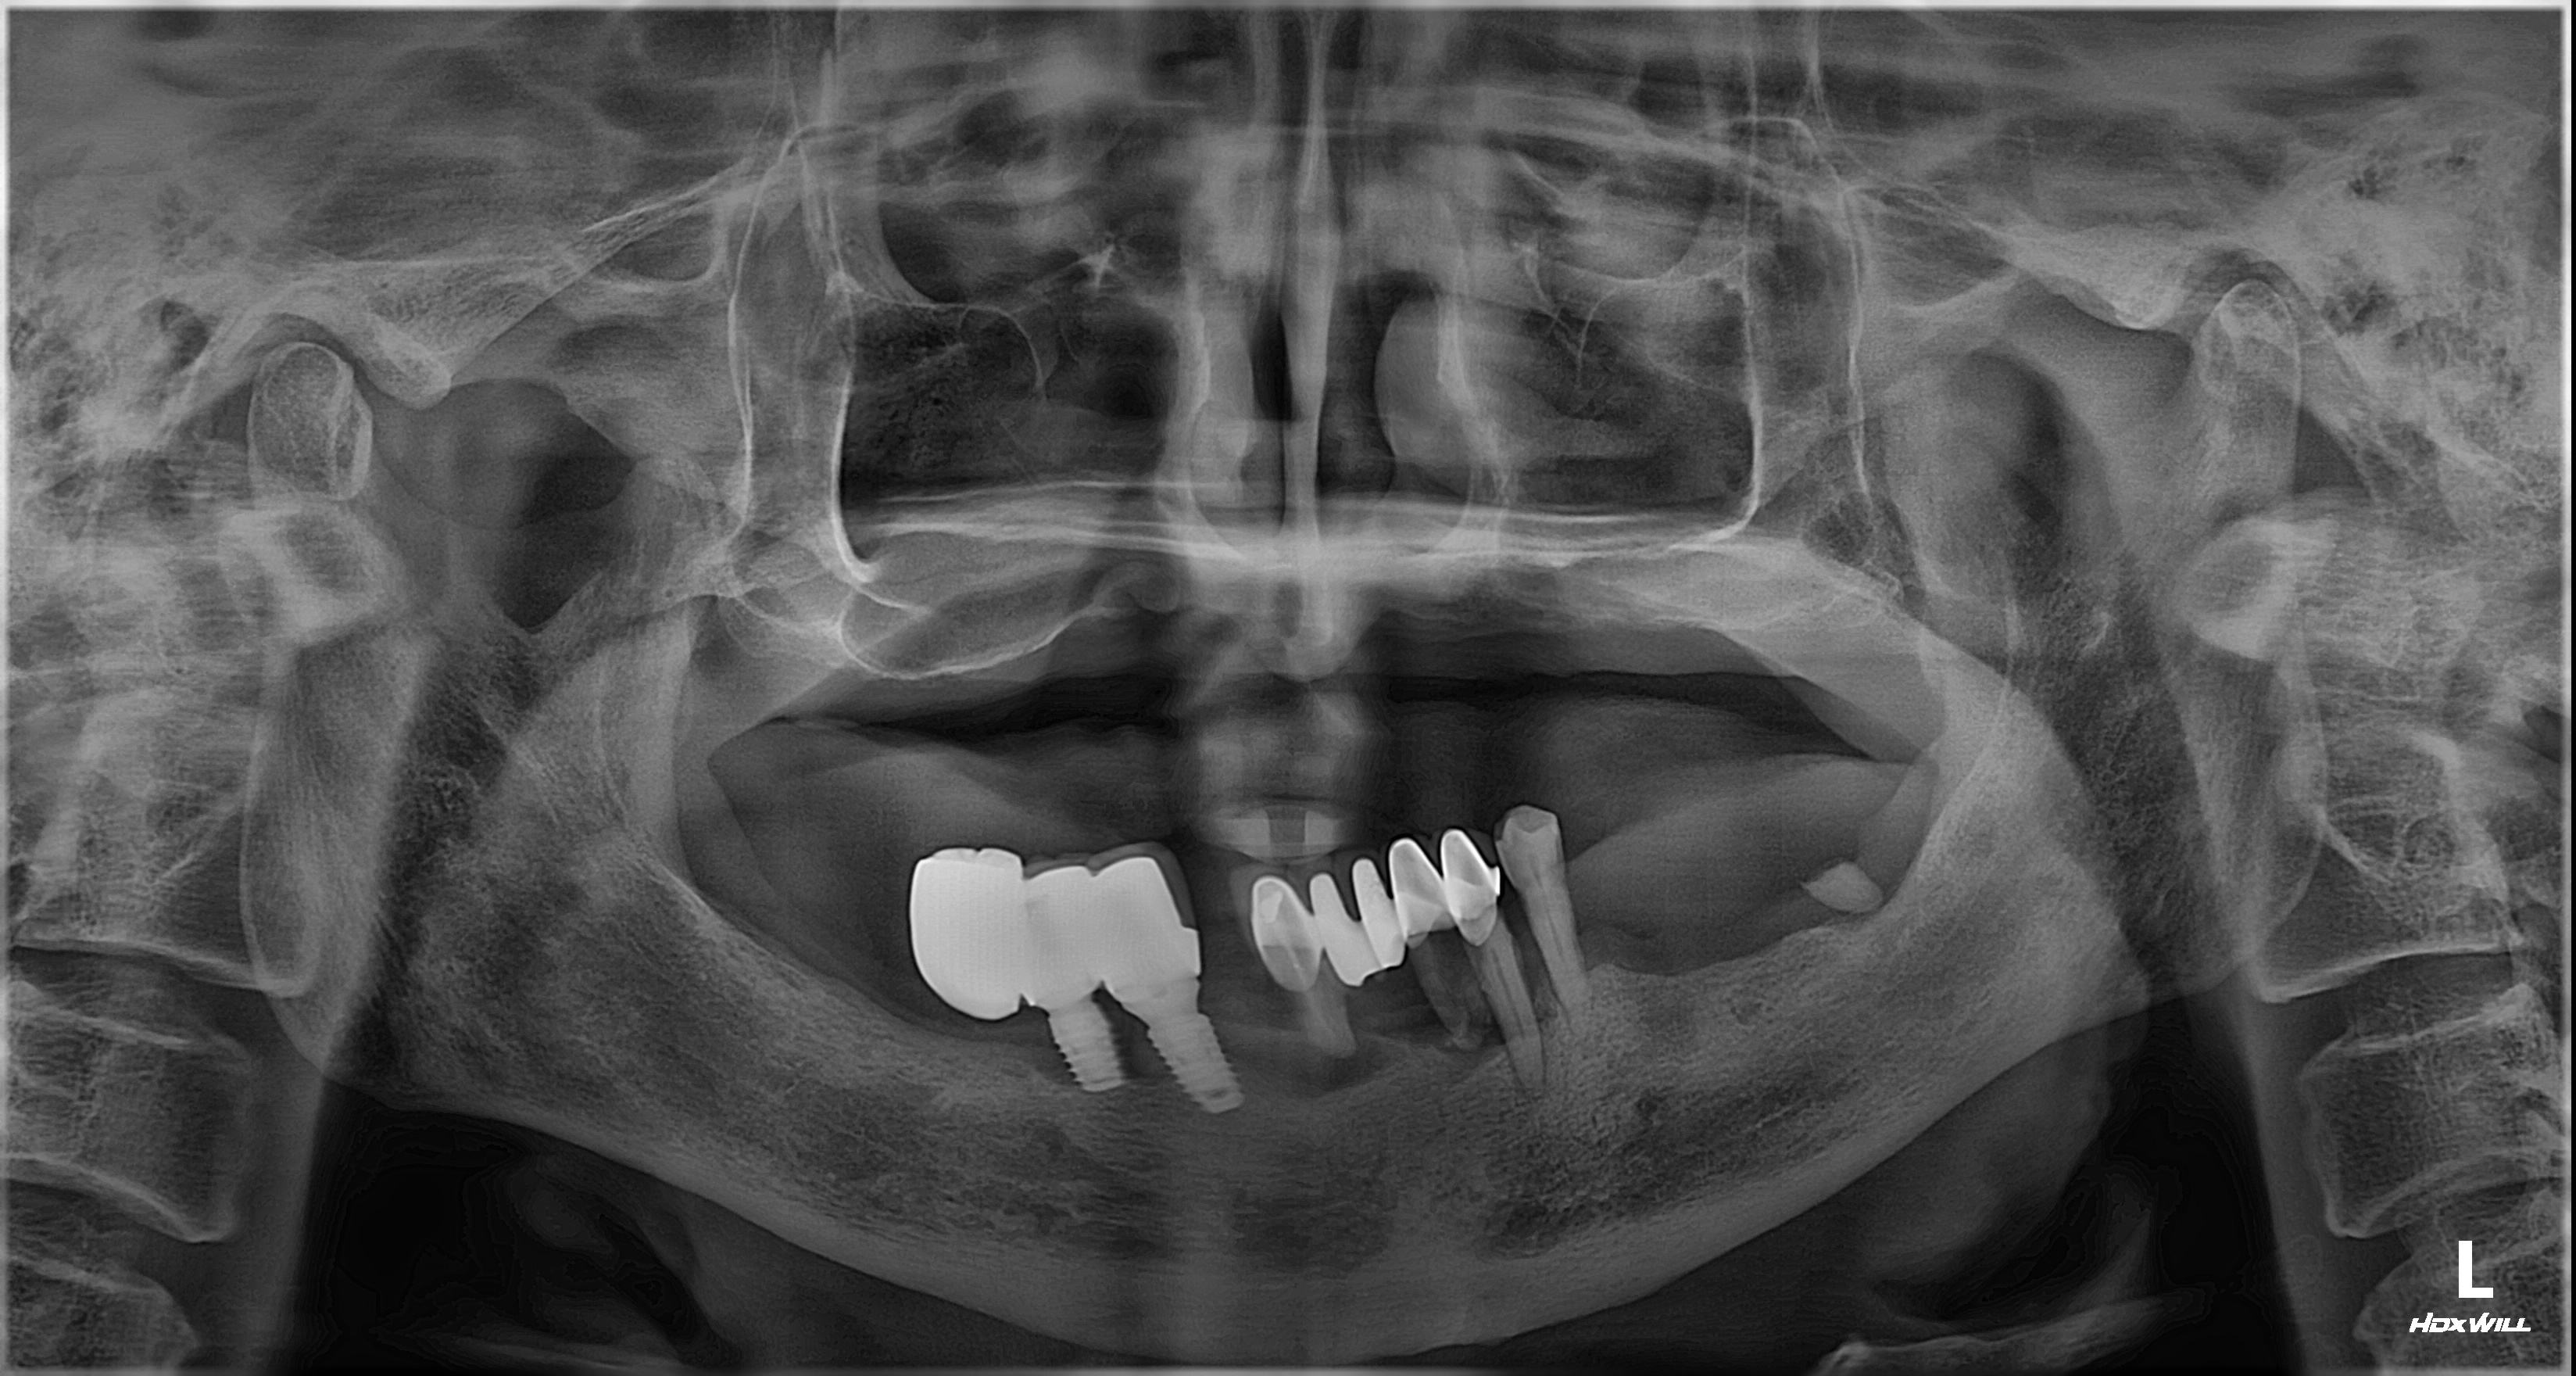

비강거상과 상악동거상을 동반한 전체임플란트 치료 증례 2026-02-20 hit.70 |

촬영일시: 2024.05.03

[ 치료기간: 2024년 05월 03일 ~2025년 03월 14일 ] ※ 365서울앞선치과의원의 모든 컬럼은 각 진료과 의료진이 직접 작성합니다. 365서울앞선치과의원 임상 케이스 게시물은 환자분께 의학적으로 정확하고 상세한 정보를 드리기 위해 각 진료과 의료진이 직접 작성하며, 모든 증례 사진은 본원 의료진이 직접 시술한 증례를 촬영한 것으로, 의료법 제23조, 제56조에 의거하며 환자분의 동의를 얻어 포스팅에 사용하였습니다. 또한 해당 케이스는 본 환자분의 치료 결과이며, 환자 상태에 따라 치료의 결과는 달라질 수 있습니다. |